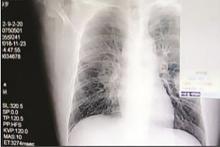

مردی در چین که عادت داشت جوراب‌هایش را هر شب بو کند، دچار عفونت ریه شد‌ و سرانجام جان باخت.

به گفته متخصصان، انواع قارچ‌ها و دیگر عوامل بیماری‌زا در جوراب‌ها وجود دارند و ذره‌ کوچکی از آنها می‌تواند موجب بیماری فردی شود که آنها را استنشاق می‌کند.